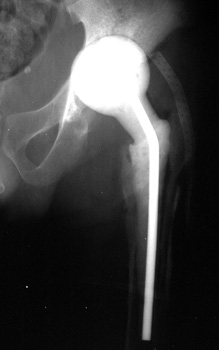

Resection of hardware, cement spacer placement

Cement spacers are antibiotic impregnated, allowing for local dispersal of antibiotics.

• Maintain leg length

• Minimize dead space

• Preserve soft tissue planes

• Facilitate ease of revision arthroplasty

Cement spacers are fabricated in the surgical suite using methylmethacralate cement impregnated with antibiotics sensitive to cultured organisms. A Rush rod is cut and bent to 120 degrees to mimic the femoral neck-shaft angle. Antibiotic impregnated cement is placed into a blue bulb syringe which simulates the femoral head contour and allowed to dry. The plastic is then removed. A second batch of cement is prepared and formed around the femoral shaft portion of the Rush rod.